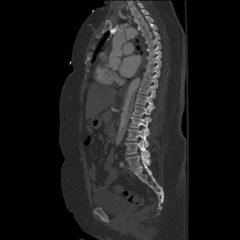

The patient’schest X-ray revealed a prominent mediastinum and opacification in the left middle and lower lung fields. The CT showed an aortic aneurysm extending from the thorax to the abdomen with rupture near T7 (blue arrow). It also showed periaortic hemorrhage with active extravasation (green arrow) likely secondary to a penetrating ulcer and bilateral pulmonary opacities concerning for hemothorax (pink arrow).